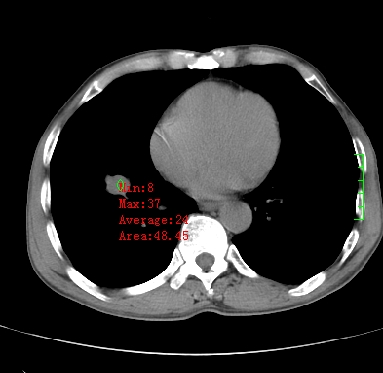

m,73y。膝关节疼痛伴双下肢水肿。入院常规胸片发现结节灶。增强为静脉期。

指套征,强化明显,近侧肺组织局限性肺气肿,考虑支气管类癌,慢支、肺气肿、双上陈旧性tb、冠脉钙化。

1)考虑右肺下叶周围型肺癌。2)右肺上叶及左肺感染性病变(结核可能)。3)肺气肿。4)冠状动脉钙化。